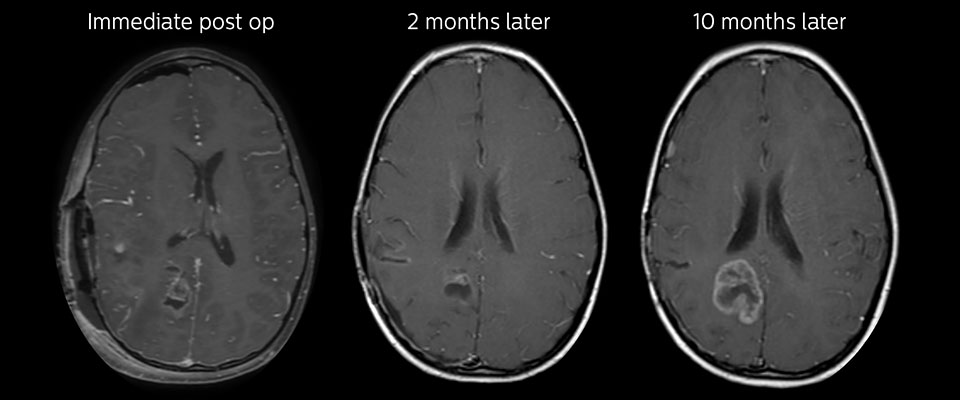

Große metastatische Hirnläsion

Diese 10-jährige Patientin unterzog sich vor 7 Jahren der Resektion eines Ewing-Sarkoms, doch jetzt wurde eine große metastatische Läsion im Gehirn entdeckt. Diese Läsion zeigt deutlich ein erhöhtes APT-Signal.

MRT mit APT nach der Resektion

Unmittelbar nach der Resektion wurde erneut eine MRT durchgeführt. Die T2-gewichteten und kontrastverstärkten T1-gewichteten Bilder lassen keine eindeutige Unterscheidung von Residualtumorgewebe und postoperativen Gewebeveränderungen zu. Auf dem APT-Bild ist noch ein hohes Signal zu sehen, das auf Residualtumorgewebe hindeuten würde.

Nachuntersuchung im Laufe der Zeit

In späteren Nachuntersuchungsscans weisen die kontrastverstärkten T1-gewichteten Bilder auf rezidivierendes Tumorwachstum hin. Daher wäre es interessant, den prädiktiven Wert von APT in einer großen Patientengruppe zu untersuchen.